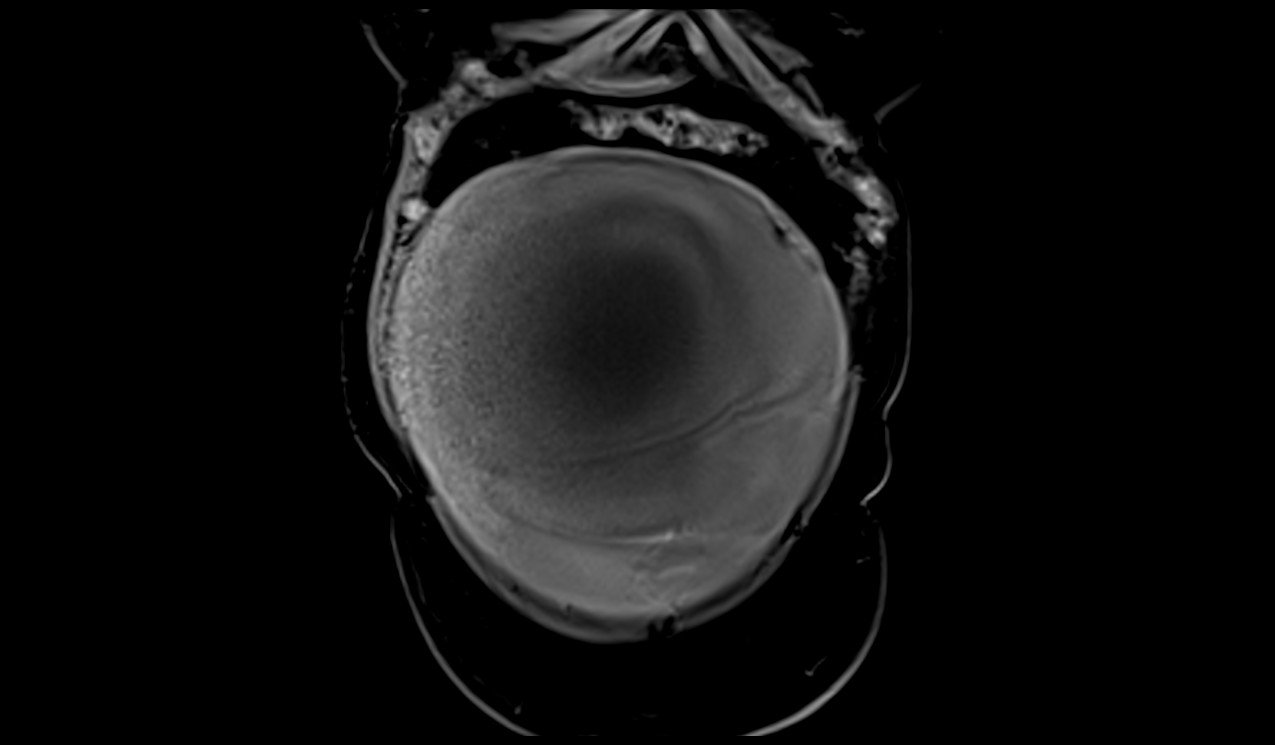

MRI Large abdomen and Pelvic Masses axial t1 dynaic image 4 - MRI